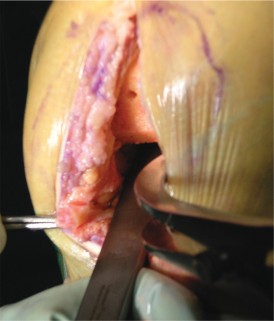

The most ubiquitous approach for TKA is the medial parapatellar arthrotomy. A straight, anterior longitudinal skin incision is made, extending from just proximal to the superior pole of the patella to just medial to the tibial tubercle. Full-thickness fasciocutaneous flaps are elevated to preserve the subdermal vascular plexus. The arthrotomy is then initiated through the medial retinaculum, coursing proximally into the quadriceps tendon (leaving a small medial cuff for later repair) and distally along the medial border of the patella and patellar tendon.

Once the joint is entered, the patella is either everted laterally or laterally subluxated, depending on the surgeon's preference and the stiffness of the extensor mechanism. A meticulous synovectomy and excision of the infrapatellar fat pad (Hoffa's fat pad) are performed to enhance visualization of the lateral compartment and the tibial plateau. All peripheral osteophytes on the femur and tibia must be aggressively resected at this stage. Retained osteophytes will artificially tension the collateral ligaments, leading to erroneous gap balancing and postoperative stiffness.